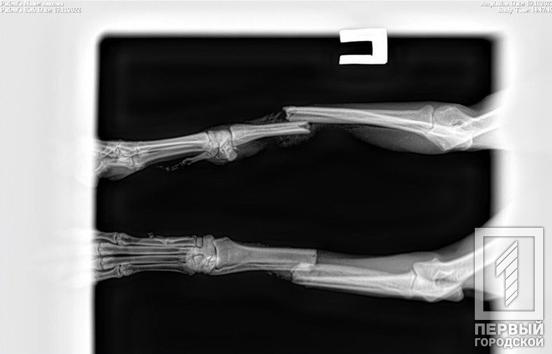

Правоохоронці зафіксували факт скоєння злочину та прийняли заяву від небайдужої криворіжанки. Тим часом, представники благодійного фонду доставили скалічену тварину до ветлікарні. Спеціалісти провели необхідні аналізи та констатували, що в результаті падіння з великої висоти собака має струс мозку, перелами кінцівок та потребує оперативного втручання, проте знаходиться у стабільному стані.